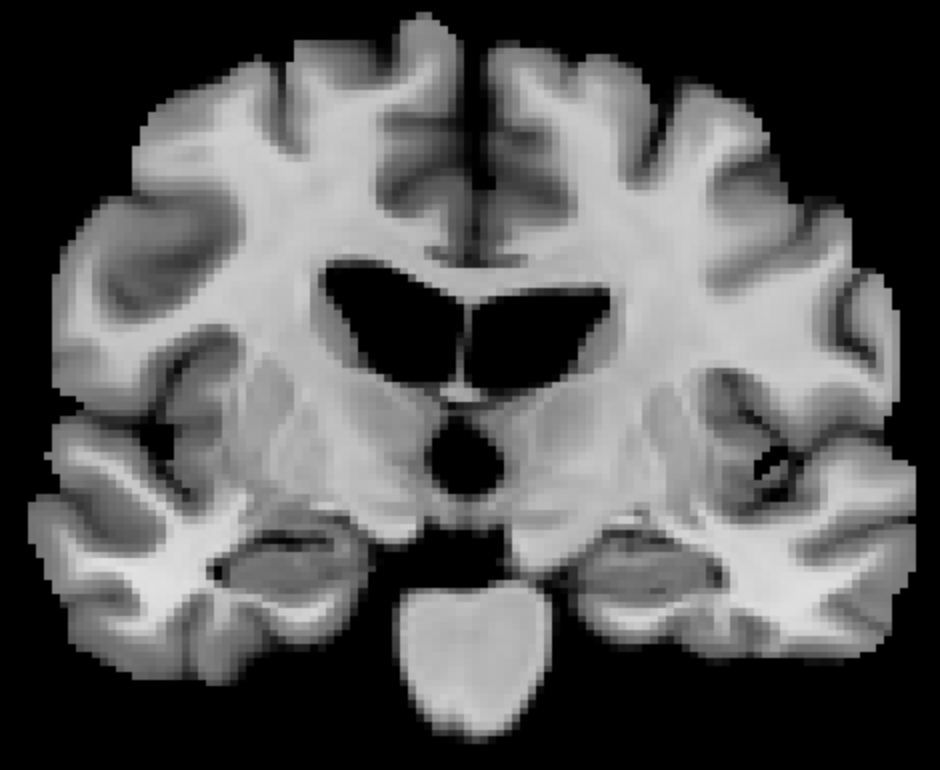

| (a) Input | (b) Sample 1 | (c) Sample 2 | (d) Sample 3 | (e) Sample 4 | (f) Seg entropy | |

| (g) Segmentation | (h) Sample 1 | (i) Sample 2 | (j) Sample 3 | (k) Sample 4 | (l) Seg entropy |